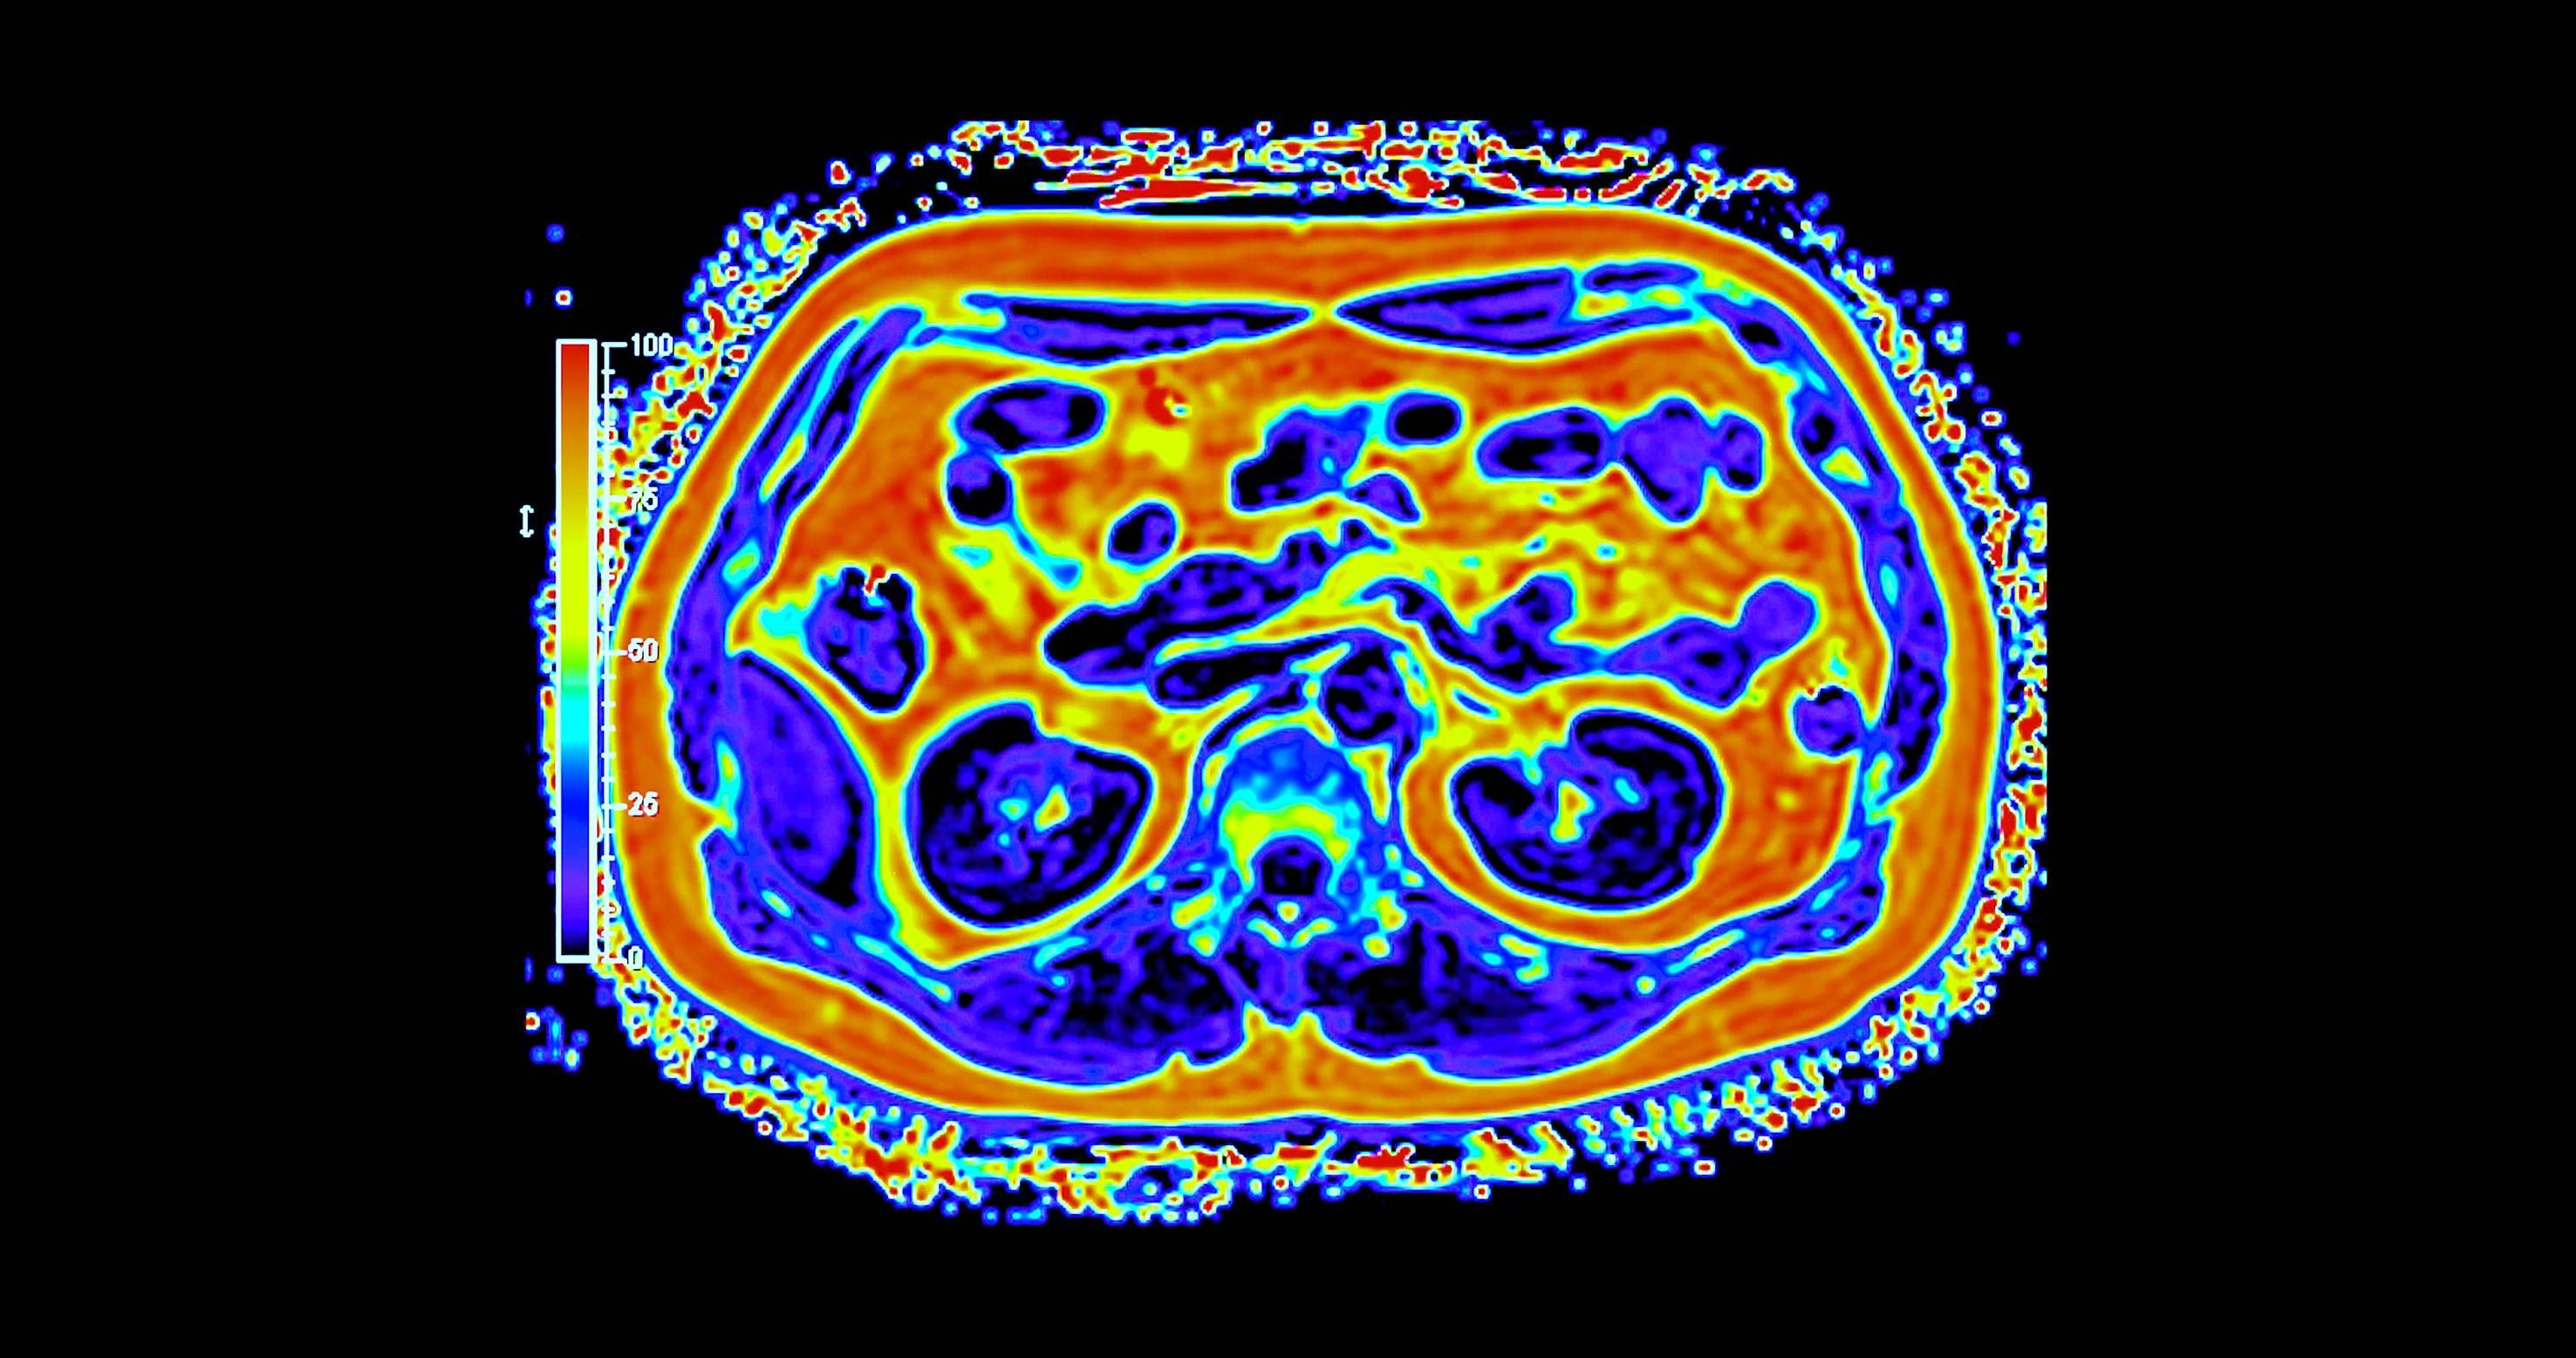

غالباً ما يُتناول تحوّل القطاع الصحي عبر محطات واضحة للعيان، مثل إنشاء مستشفيات جديدة، وإطلاق منصات رقمية، واعتماد أجهزة طبية متقدمة. غير أنّ جانباً أقل ظهوراً وأكثر حسماً يتمثل في بناء بنية تحتية تشخيصية قادرة على دعم الاكتشاف المبكر والطب الدقيق والرعاية الوقائية على نطاق وطني. ويقع التصوير الجزيئي، ولا سيما التقنيات الهجينة، مثل «PET - MRI» في صميم هذا التحول.

وعلى خلاف التصوير التقليدي، يجمع التصوير الجزيئي بين التفاصيل التشريحية والبيانات الوظيفية الآنية، ما يتيح للأطباء رؤية كيفية عمل الأنسجة لا مجرد شكلها. وفي مجالَي الأورام والأمراض العصبية، قد يُحدث هذا الفرق تحولاً في توقيت الاكتشاف أو في تعديل خطط العلاج أو في تجنّب إجراءات غير ضرورية. غير أن توسيع هذه القدرات عبر بلد واسع ومتنوّع جغرافياً يطرح تحديات تتجاوز كثيراً مجرد اقتناء الأجهزة.

أحرزت السعودية تقدماً تدريجياً في نشر أنظمة التصوير المتقدم، بما في ذلك «PET - CT» و«PET - MRI» داخل مراكز طبية كبرى. وبحسب الدكتور سامح الشيخ المدير العام لشركة التصوير الجزيئي والقطاع الطبي بوادي جدة، أثبتت هذه التقنيات قيمتها السريرية عبر الكشف عن انتشار سرطاني أو اضطرابات لم تُظهرها وسائل التصوير التقليدية، ما أتاح تعديل العلاج فوراً في عدد من الحالات.